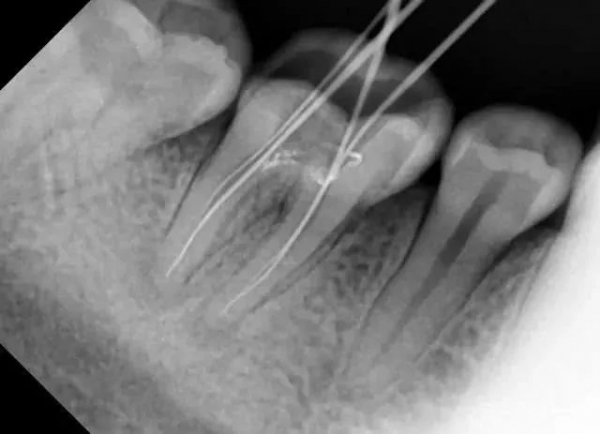

- 比如當(dāng)牙齒有深部齲壞時,僅憑口內(nèi)檢查無法得知齲洞的深度、離牙神經(jīng)的距離以及有沒有并發(fā)牙根發(fā)炎等重要信息。

- 比如,當(dāng)拔除下頜智齒時,僅憑口內(nèi)檢查無法發(fā)現(xiàn)它離神經(jīng)管的位置

因此,如果牙齒出了問題,齒科醫(yī)生就需要有“透視”功能的X線片來檢查。通過x線片不僅能了解牙齒本身的病變情況,還可以了解牙根下有沒有囊腫、周圍骨頭有沒有吸收以及牙槽骨內(nèi)是否有埋伏牙、多生牙等。依據(jù)X線片綜合分析,可以提高齒科醫(yī)生診斷治療牙齒的準(zhǔn)確性和成功率。常見的牙科放射檢查包括曲面體層片( 全景片 )、小牙片、頭顱正側(cè)位片、全頭顱 CT、錐形束 CT( CBCT )等。由于牙齒下部隱藏在牙槽骨中,口腔醫(yī)生要了解牙齒的整體情況就需要拍攝全景片;要了解個別牙根及周圍變化,則選擇拍攝小牙片。醫(yī)生要判斷牙槽骨是否符合種植條件,或者了解埋伏阻生齒的三維位置以及其他頜骨內(nèi)病變組織的形態(tài)大小時,則需要進(jìn)一步拍攝 CBCT 。所以,拍牙片是一種幫助齒科醫(yī)生進(jìn)行診斷、治療、療效評估的重要手段,治療前用于發(fā)現(xiàn)病變程度、范圍;治療中用于引導(dǎo)治療、確定治療范圍和深度;治療后用于觀察療效。輻射分為電離輻射(如X光)和非電離輻射(如手機(jī)、微波爐),這里主要講述的是電離輻射。電離輻射的測量單位是西弗(Sv),但西弗是個非常大的單位,因此通常使用毫西弗(mSv)和微西弗(μSv),1Sv=1000mSv,1mSv=1000μSv)根據(jù)國際放射防護(hù)委員會(IRPA)提供的信息,每人每年受到的輻射劑量大約在2.5毫西弗左右,這個數(shù)值受地域緯度的影響而波動。其中大約80%來源于自然界,20%來源于人工輻射。而拍牙片是什么樣的輻射水平呢?根尖片為 5.2 μSv ,全口根尖片為 72.32 μSv ,曲面體層片為 10 ~ 23 μSv ,頭顱正位片為 1 ~ 5 μSv ,頭顱側(cè)位片為 1 ~ 3 μSv ,讓人「聞風(fēng)喪膽」的 CBCT 劑量一般也在 300 μSV 之內(nèi)。為了幫助大家更容易理解,我們用單位面積內(nèi)的香蕉數(shù)量表達(dá)輻射強(qiáng)度。之所以選擇香蕉,是因為香蕉富含鉀元素,天然鉀當(dāng)中約有0.0117%的放射性鉀——鉀40,而鉀40的半衰期長達(dá)12億5千萬年(地球歲數(shù)大約45億年)。